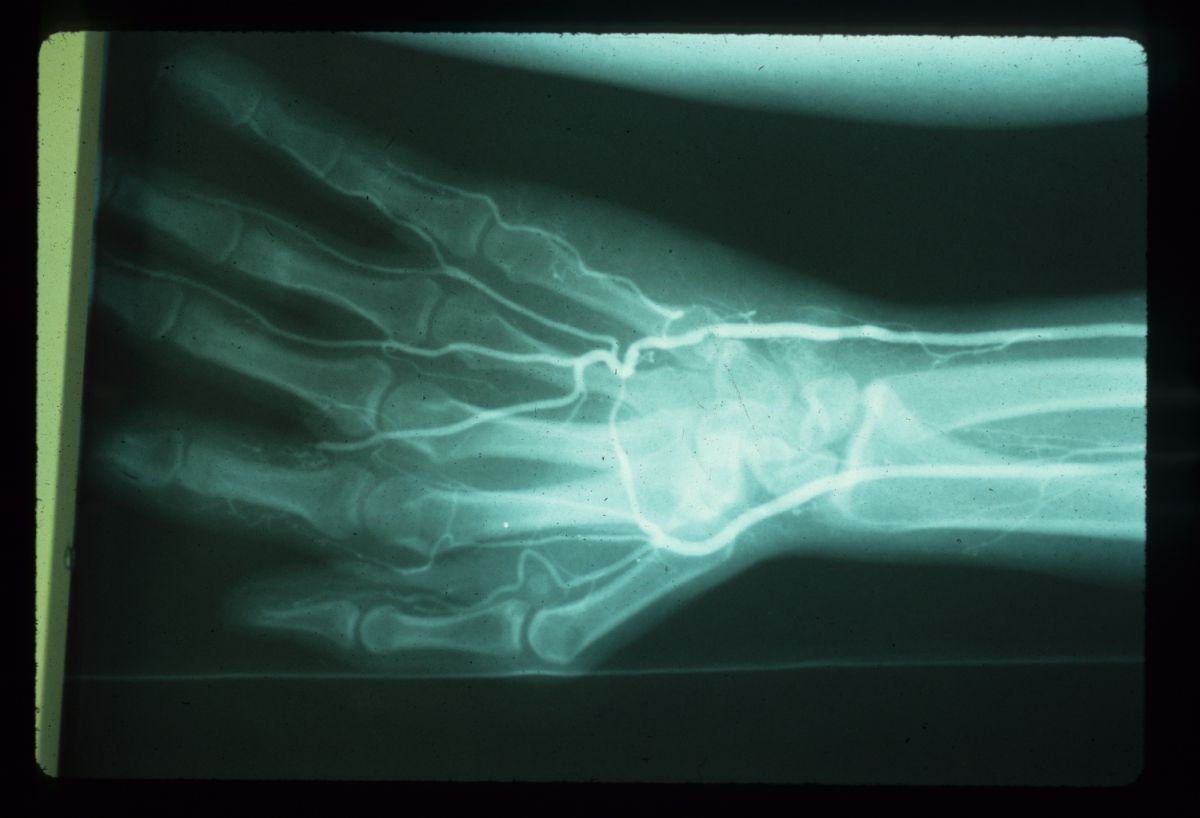

| Case 2. This patient developed

ischemia of the radial aspect of her left hand during a carotid

endarterectomy. These pictures were taken four weeks postop. |

| Imaging demonstrated

nonreconstructible vascular disease. |